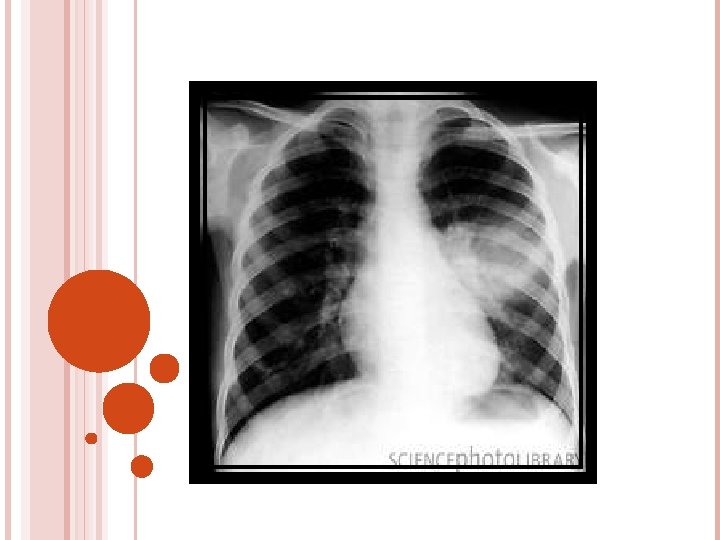

DIAGNOSTIC STUDIES History collection , physical examination Chest X-Ray lab Microbiology serology ABG

CLINICAL FEATURES Progressive dyspnea Decreased movement of chest wall on affected side Pleuritic pain Dullness on percussion Absent or decreased breath sounds